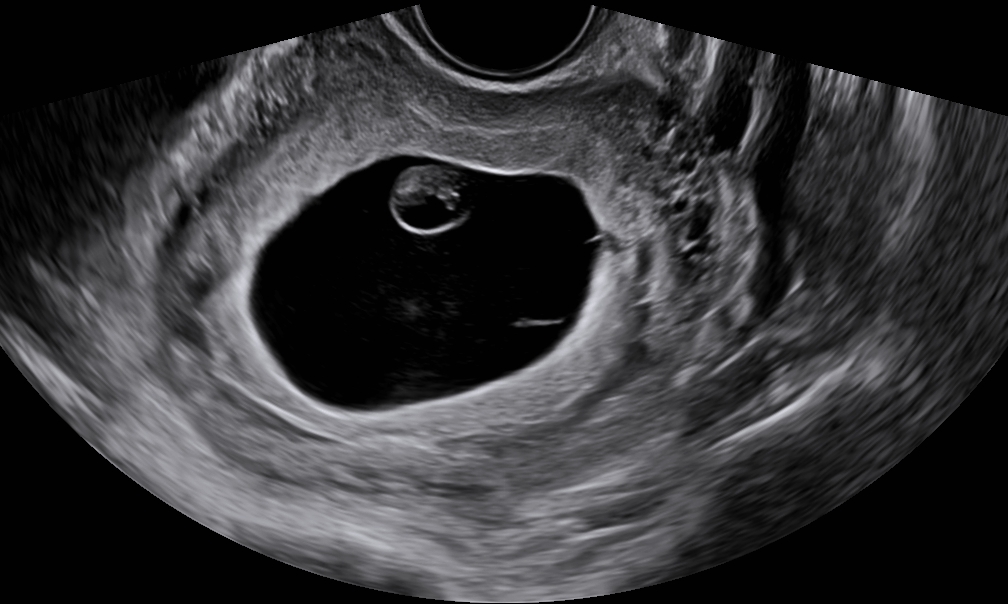

Auto OB automatically measures the common fetal biometric results (HC, BPD, FL, etc.) in standard sections.

Auto NT automatically recognizes and measures the thickness of the fetal nuchal translucency.

Lumi 4D enables the adjustment of light source angle to support real-time static stereo imaging of the fetus.